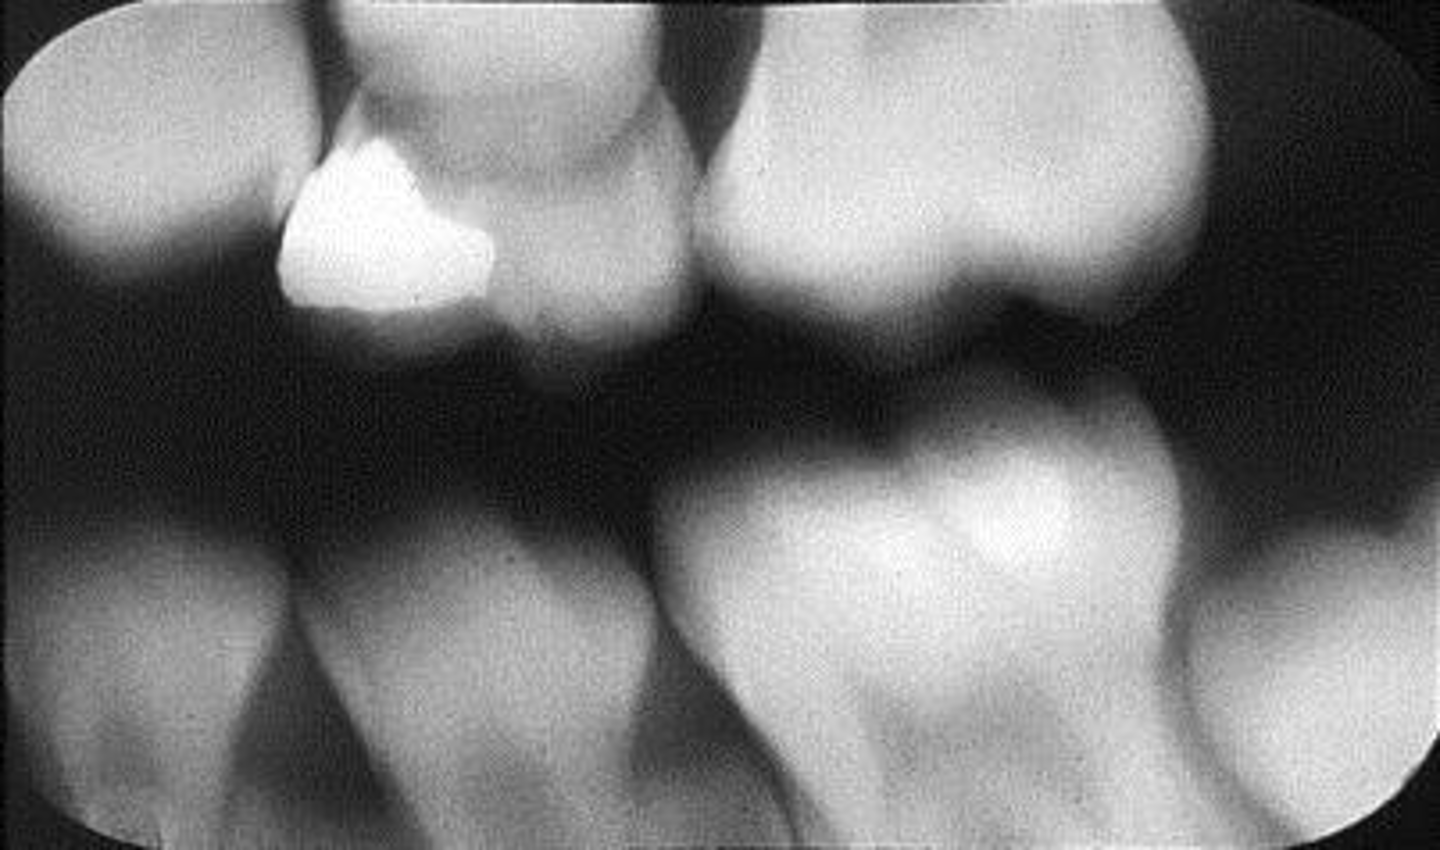

What is this error?

Cone cut, rotation